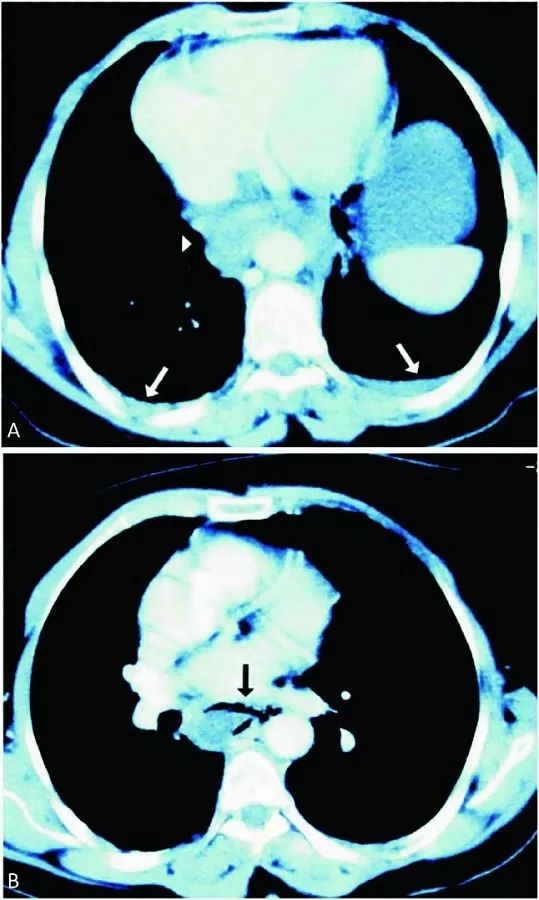

再次行CT扫描颈部和胸部,发现右侧扁桃体软组织肿胀,扁桃体周围和咽后间隙多发脓肿并向下延伸至上纵膈(图4)。考虑诊断纵膈炎、脓肿形成,立即插入胸管引流并急诊开胸手术。最终,患者因脓毒症导致多脏器衰竭,在入院第20天死亡。

图4 发病5天后CT(右上图白色箭头:气管周围多个脓肿,短黑箭头:气管,黑长箭头:上腔静脉;右下图白色箭头:脓肿沿降主动脉向下延伸)